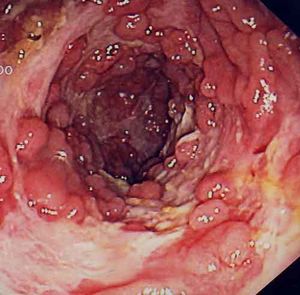

مرض كرون

مرض كرون ، المعروف أيضا باسم مرض التهاب الأمعاء ، التهاب الأمعاء الإقليمية ، و مرض التهاب اللفائفي و القولون الحبيبي هو مرض التهاب الأمعاء التي قد تؤثر على أي جزء من الجهاز الهضمي من الفم إلى فتحة الشرج ، مما تسبب في طائفة واسعة من الأعراض. فإنه يتسبب في المقام الأول آلام في البطن و الاسهال (التي قد تكون دامية إذا التهاب في أسوأ حالاته) ، و القيء ، أو فقدان الوزن ، ولكن قد يسبب مضاعفات أيضا خارج الجهاز الهضمي مثل الطفح الجلدي ، التهاب المفاصل ، والتهاب في العين ، وعدم القدرة على التركيز.